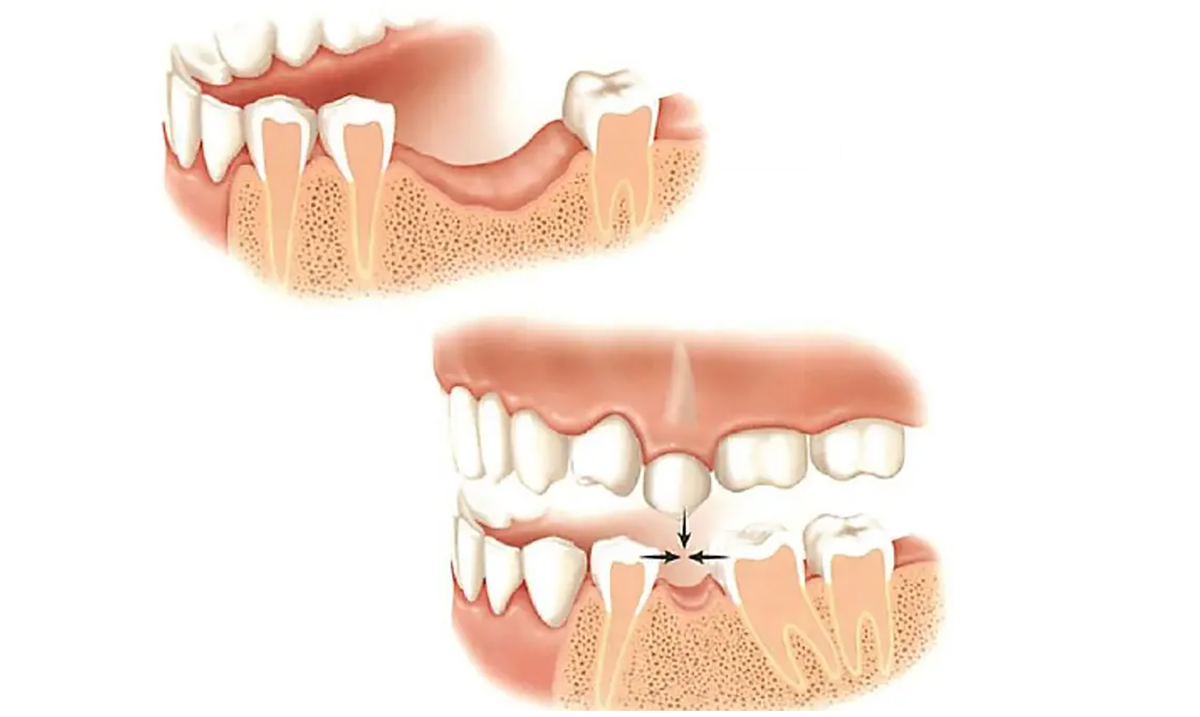

Implantul dentar este o piesă din titan pur, având, în general, forma de șurub. El are menirea de a crea o rădăcină artificială în osul maxilar, acolo unde dintele sau dinții naturali lipsesc. Reconstrucția este formată din două segmente — unul intra-osos (implantul) și unul supra-osos numit bont protetic. Deasupra bontului protetic se ancorează o coroană, o punte sau o proteză. Tratamentul este conservator în comparație cu o lucrare tradițională prin punte, deoarece implanturile dentare elimină necesitatea sacrificării dinților învecinați. În cazul în care confecționăm o punte dentară, aceasta are nevoie pentru ancorare de minimum 2 dinți stâlpi, dinți ce vor fi din păcate sacrificați (se extrag nervii, se obturează canalele și se șlefuiesc dinții care odinioară erau sănătoși).

- Pentru a păstra intangibili dinții vecini în timpul protezării. Adică evităm șlefuirea dinților vecini păstrându-i sănătoși cât mai mult timp.